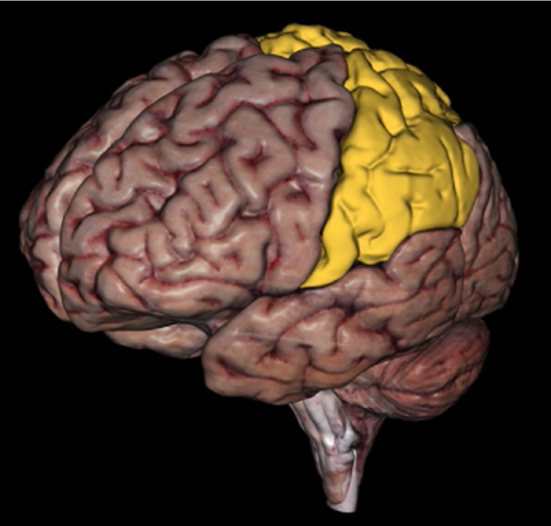

Parietal Lobe

Parietal Lobe